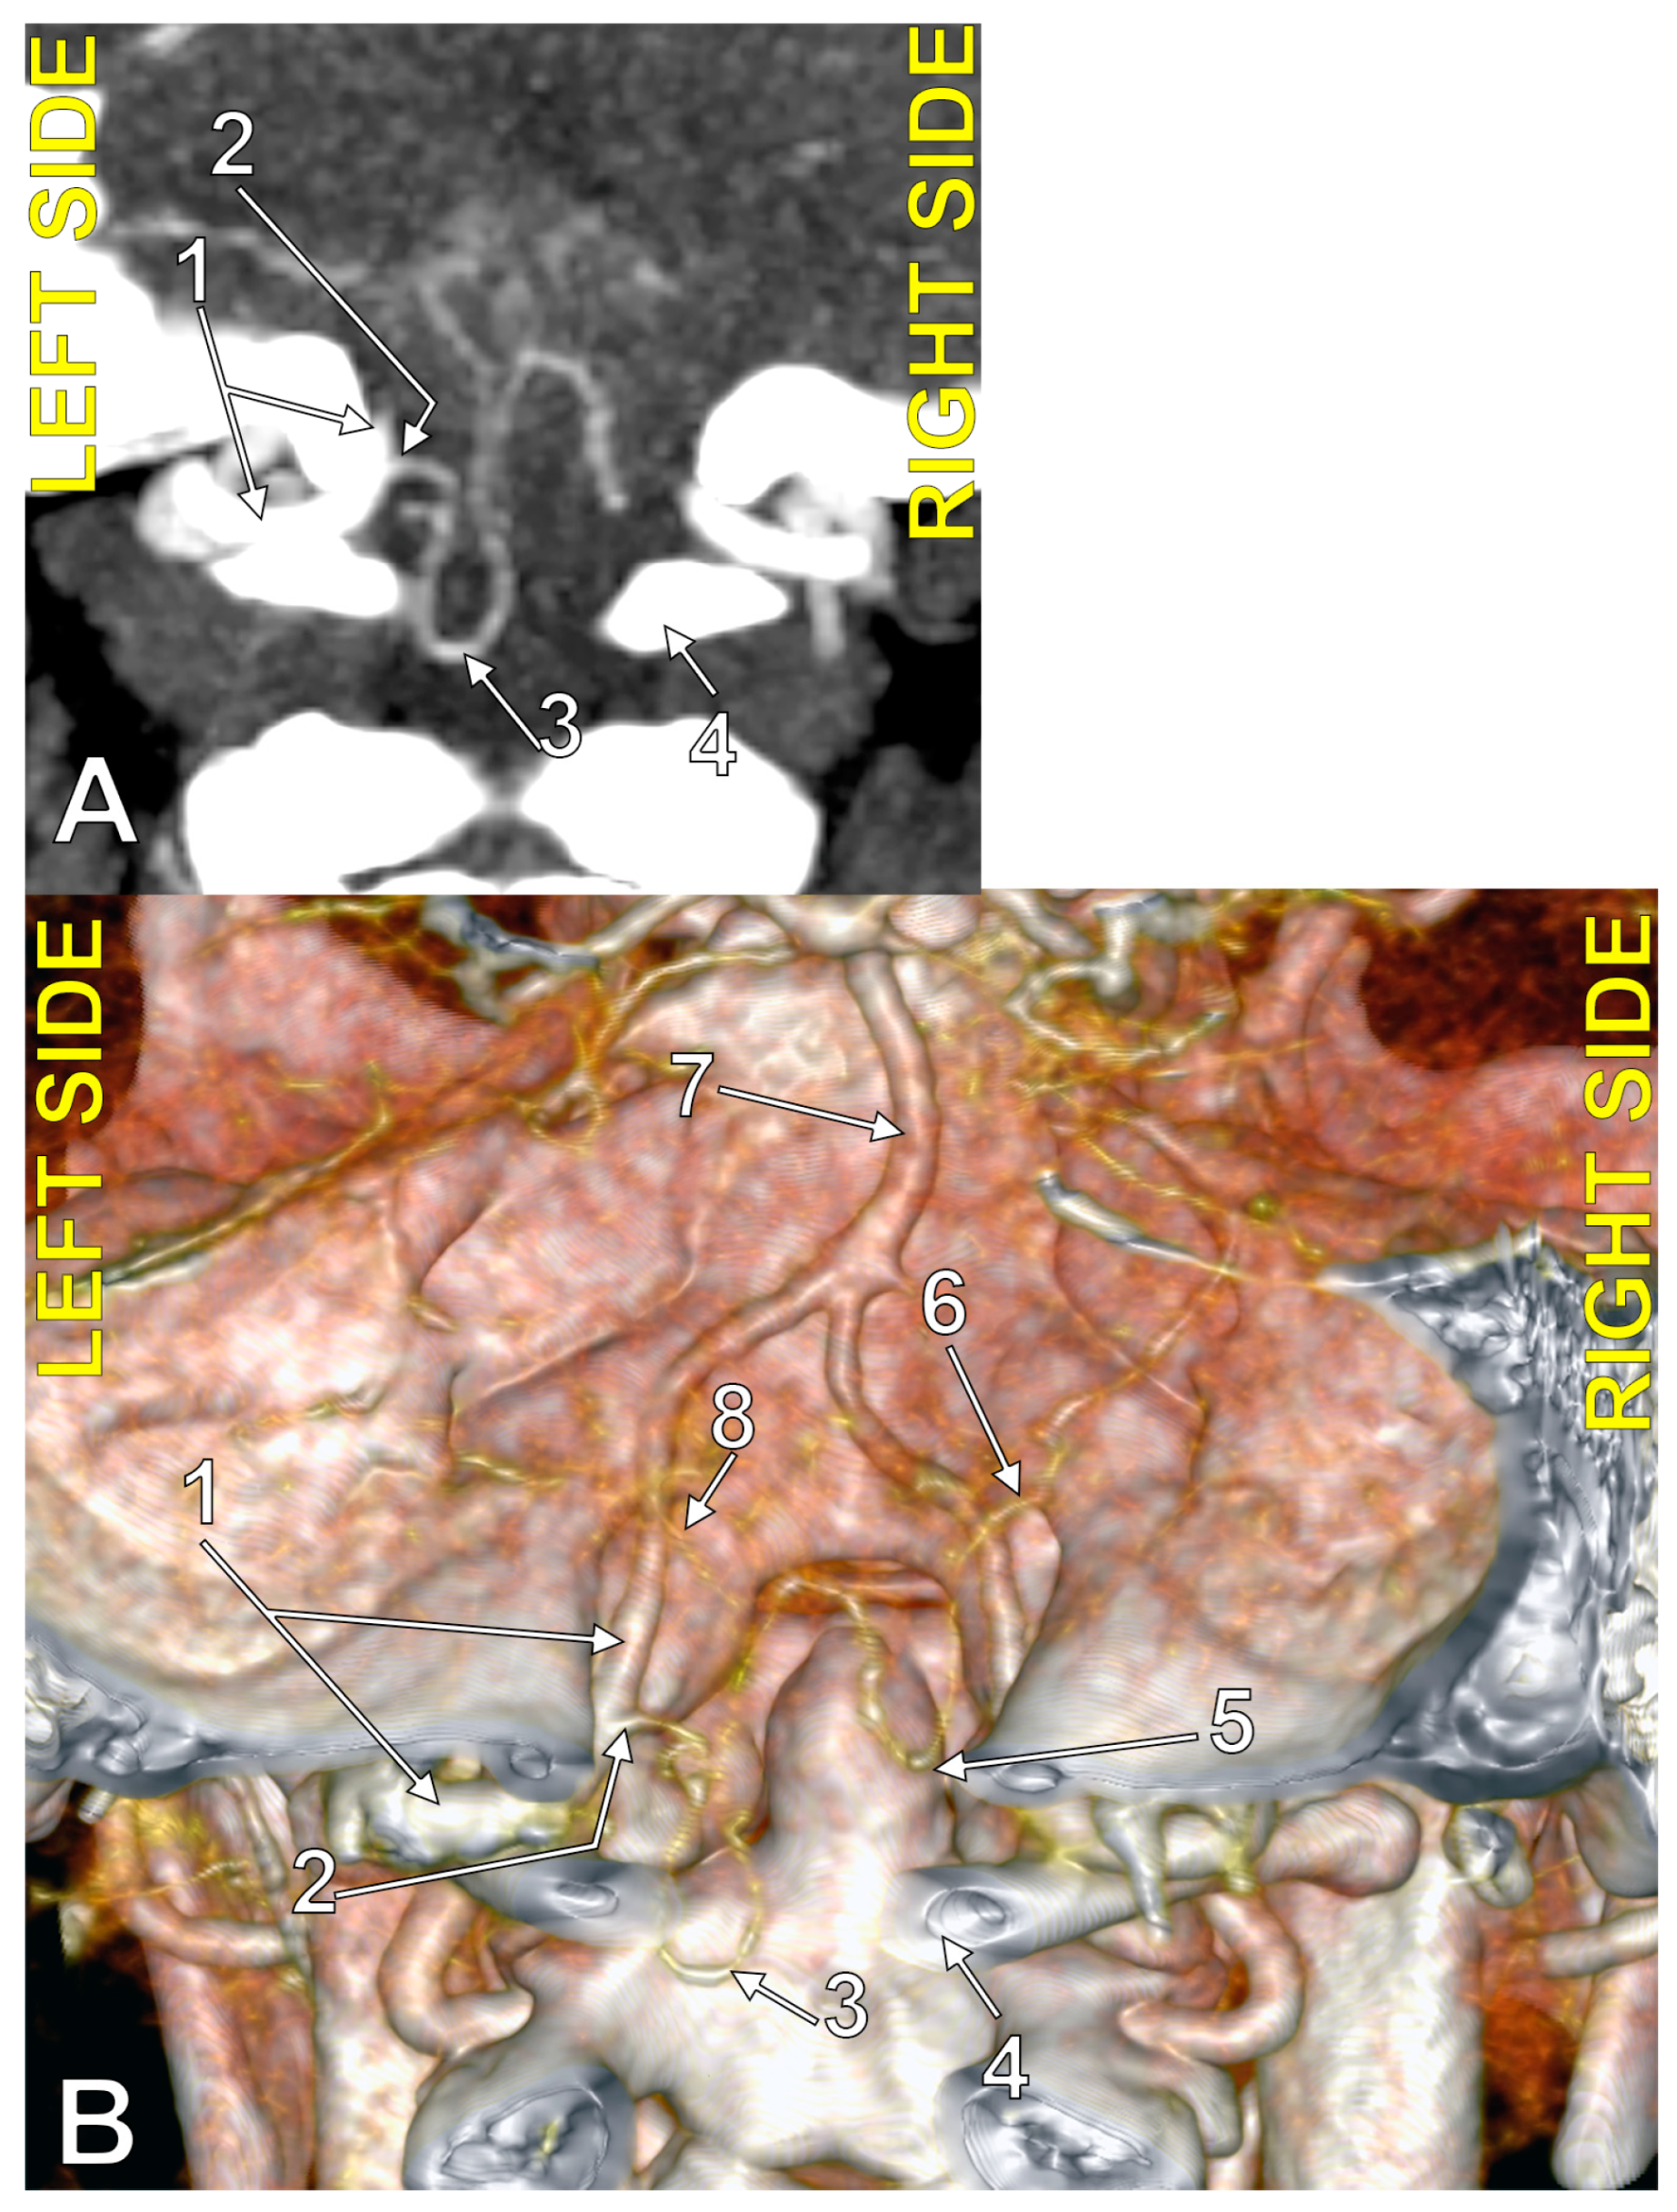

4.5. The PICA and the Marginal Sinus

4.6. The PICA and the Dural Ring of the VA